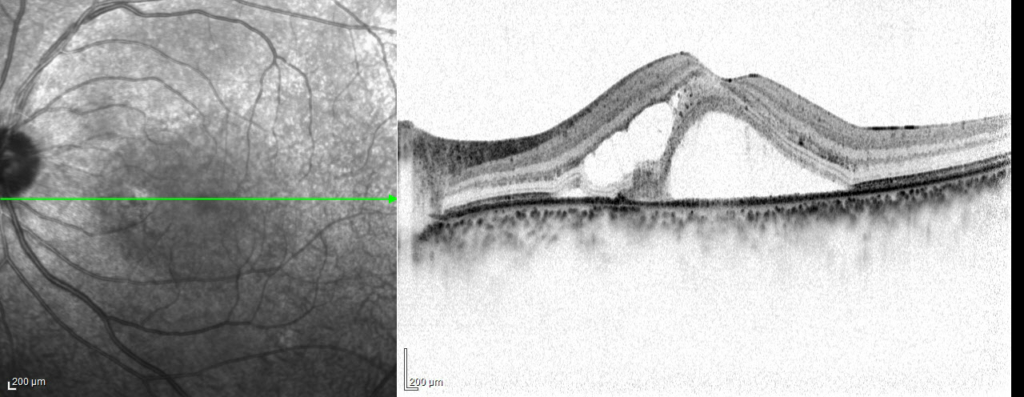

耳側下方弁状裂孔による網膜剥離

60歳 女性主訴 3週間ほど前から飛蚊症、1週間前から視力低下を自覚視力 左眼 0.09(n.c) 硝子体手術(経毛様体扁平部硝子体切除 Pars Plana Vitrectomy:PPV、眼内レーザー、20%SF6ガス置換)+水晶体再建術を行った。 3時から8時に黄斑剥離を伴う胞状...